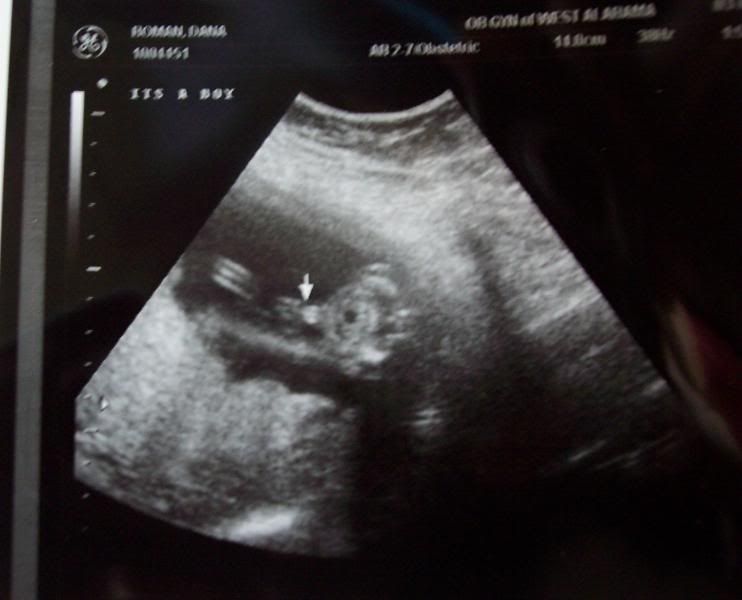

Danalana wrote: Well, we got ANOTHER gender confirmation...definitely boy  Carter weighs about 11 ounces and is perfect! All of his organs check out just fine and the blood flow in the cord is great I had to lie on both sides, eventually (not at once, LOL!), because he was wanting to stay on one side with his legs bunched up. The tech said "Look at all the room he has on your left side, and he doesn't care a thing about it" Anyway, here are a few pictures. The quality isn't that great because I took pictures of the prints with my camera. Oh, and I am a little bummed that I didn't get a profile picture...they gave me 2 really good ones with Kade. Oh well, we got the DVD and have watched it 3 times so far

I'm a BOY!